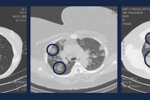

Do internetu trafił list wirusologa, w którym lekarz radzi swoim przyjaciołom jak postępować teraz i w trakcie epidemii wywołanej koronawirusem. Sprawdzamy jakie rady się w nim znajdują i czy wszystkie są słuszne.

Czy kobiety w ciąży są bardziej narażone zna zarażenie się koronawirusem? Czy noworodek może zarazić się wirusem Sars-CoV-2 od mamy w czasie porodu?

Koronawirus jest już w Polsce. Co można robić i jak się zabezpieczać przed wirusem Sars-CoV-2? Kiedy i komu jest potrzebna maseczka na twarz?